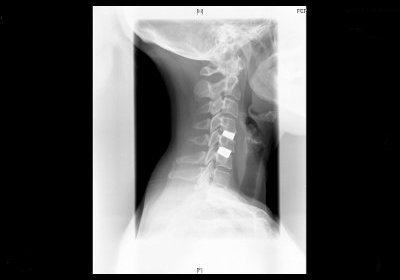

Columna cervical